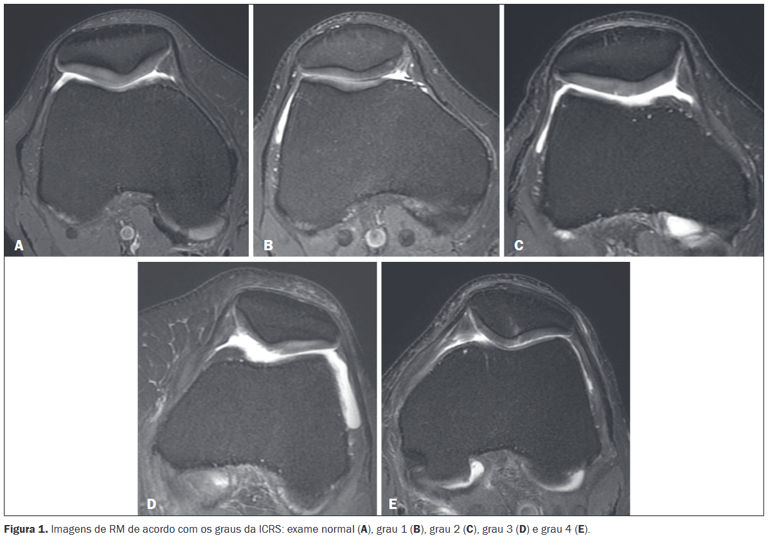

O diagnóstico clínico (médico) frequentemente vem a partir de exames de ressonância magnética, onde podemos classificar a condropatia como graus I, II, III e IV, onde o grau I seria o de menor gravidade e o grau IV seria o de maior gravidade.

Fonte: Krieger e colaboradores (2019)